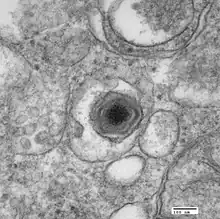

Electron micrograph of a virus particle

ASFV is a large (175–215 nm),[6] icosahedral, double-stranded DNA virus with a linear genome of 189 kilobases containing more than 180 genes.[7] The number of genes differs slightly among different isolates of the virus.[8] ASFV has similarities to the other large DNA viruses, e.g., poxvirus, iridovirus, and mimivirus. In common with other viral hemorrhagic fevers, the main target cells for replication are those of monocyte, macrophage lineage. Entry of the virus into the host cell is receptor-mediated, but the precise mechanism of endocytosis is presently unclear.[9]

The virus encodes enzymes required for replication and transcription of its genome, including elements of a base excision repair system, structural proteins, and many proteins that are not essential for replication in cells, but instead have roles in virus survival and transmission in its hosts. Virus replication takes place in perinuclear factory areas. It is a highly orchestrated process with at least four stages of transcription—immediate-early, early, intermediate, and late. The majority of replication and assembly occurs in discrete, perinuclear regions of the cell called virus factories, and finally progeny virions are transported to the plasma membrane along microtubules where they bud out or are propelled away along actin projections to infect new cells. As the virus progresses through its lifecycle, most if not all of the host cell's organelles are modified, adapted, or in some cases destroyed.

Macrophage cell in early stages of infection with ASFV